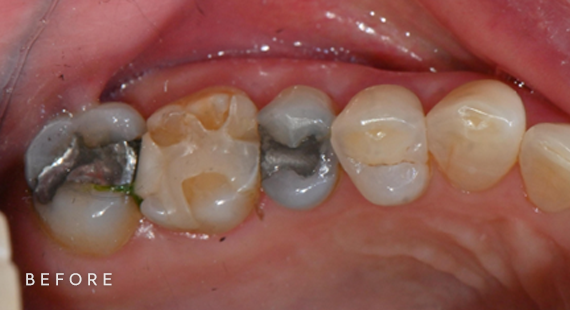

충치치료